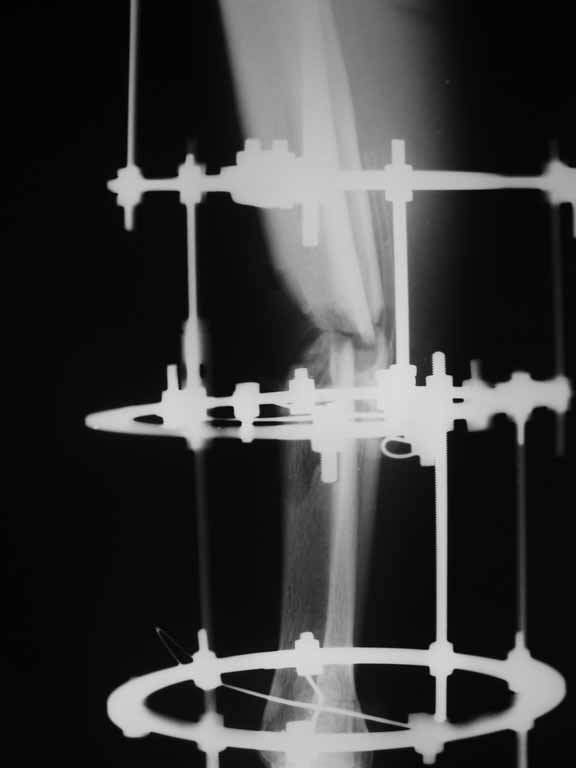

Извините, не загрузились сразу все рентгенограммы.

Внедрение одного отломка в другой приведет к укорочению. Резекция с выращиванием резко удлинит срок лечения, вероятно, потребуются еще какие-то операции после завершения дистракции... А самое главное, это избыточные действия. Ведь дефект не сегментарный, краевой контакт есть.

Вполне достаточно закрытого интрамедуллярного остеосинтеза без открытых вмешательств в зоне стыка. Конечно, с рассверливанием. Если есть опасения насчет инфекции, то на гвоздь нанести цемент с ванкомицином.

Гвоздь тут будет эндопротезом диафиза на достаточное время для образования сращения в зоне имеющегося небольшого контакта. И далее страховкой от рефрактур.